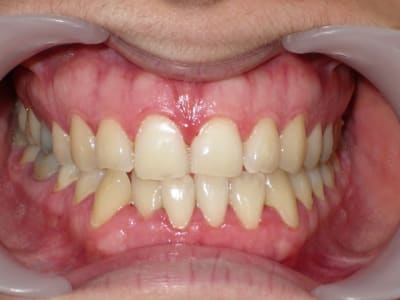

voici de la cas d'un jeune dame de 23 ans qui présente une full classe III subdivision Droite (associée à des compensations incisives de classe III), sur un terrain hyperdivergent. on note un encombrement inferieur d'environ 2 mm et une abrasion des bords triturants des incisives inf (Motif de la consultation)

on notera egalement de face une déviation de la pointe du menton vers la gauche.

"une abrasion des bords triturants des incisives inf (Motif de la consultation)"

c'est pas les incisives sup plutôt ?